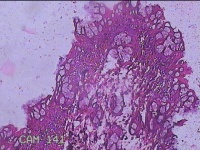

直肠粘膜

直肠黏膜水肿,血管网消失,近肛门可见片状糜烂。

灰白粉红色组织小米大一团。